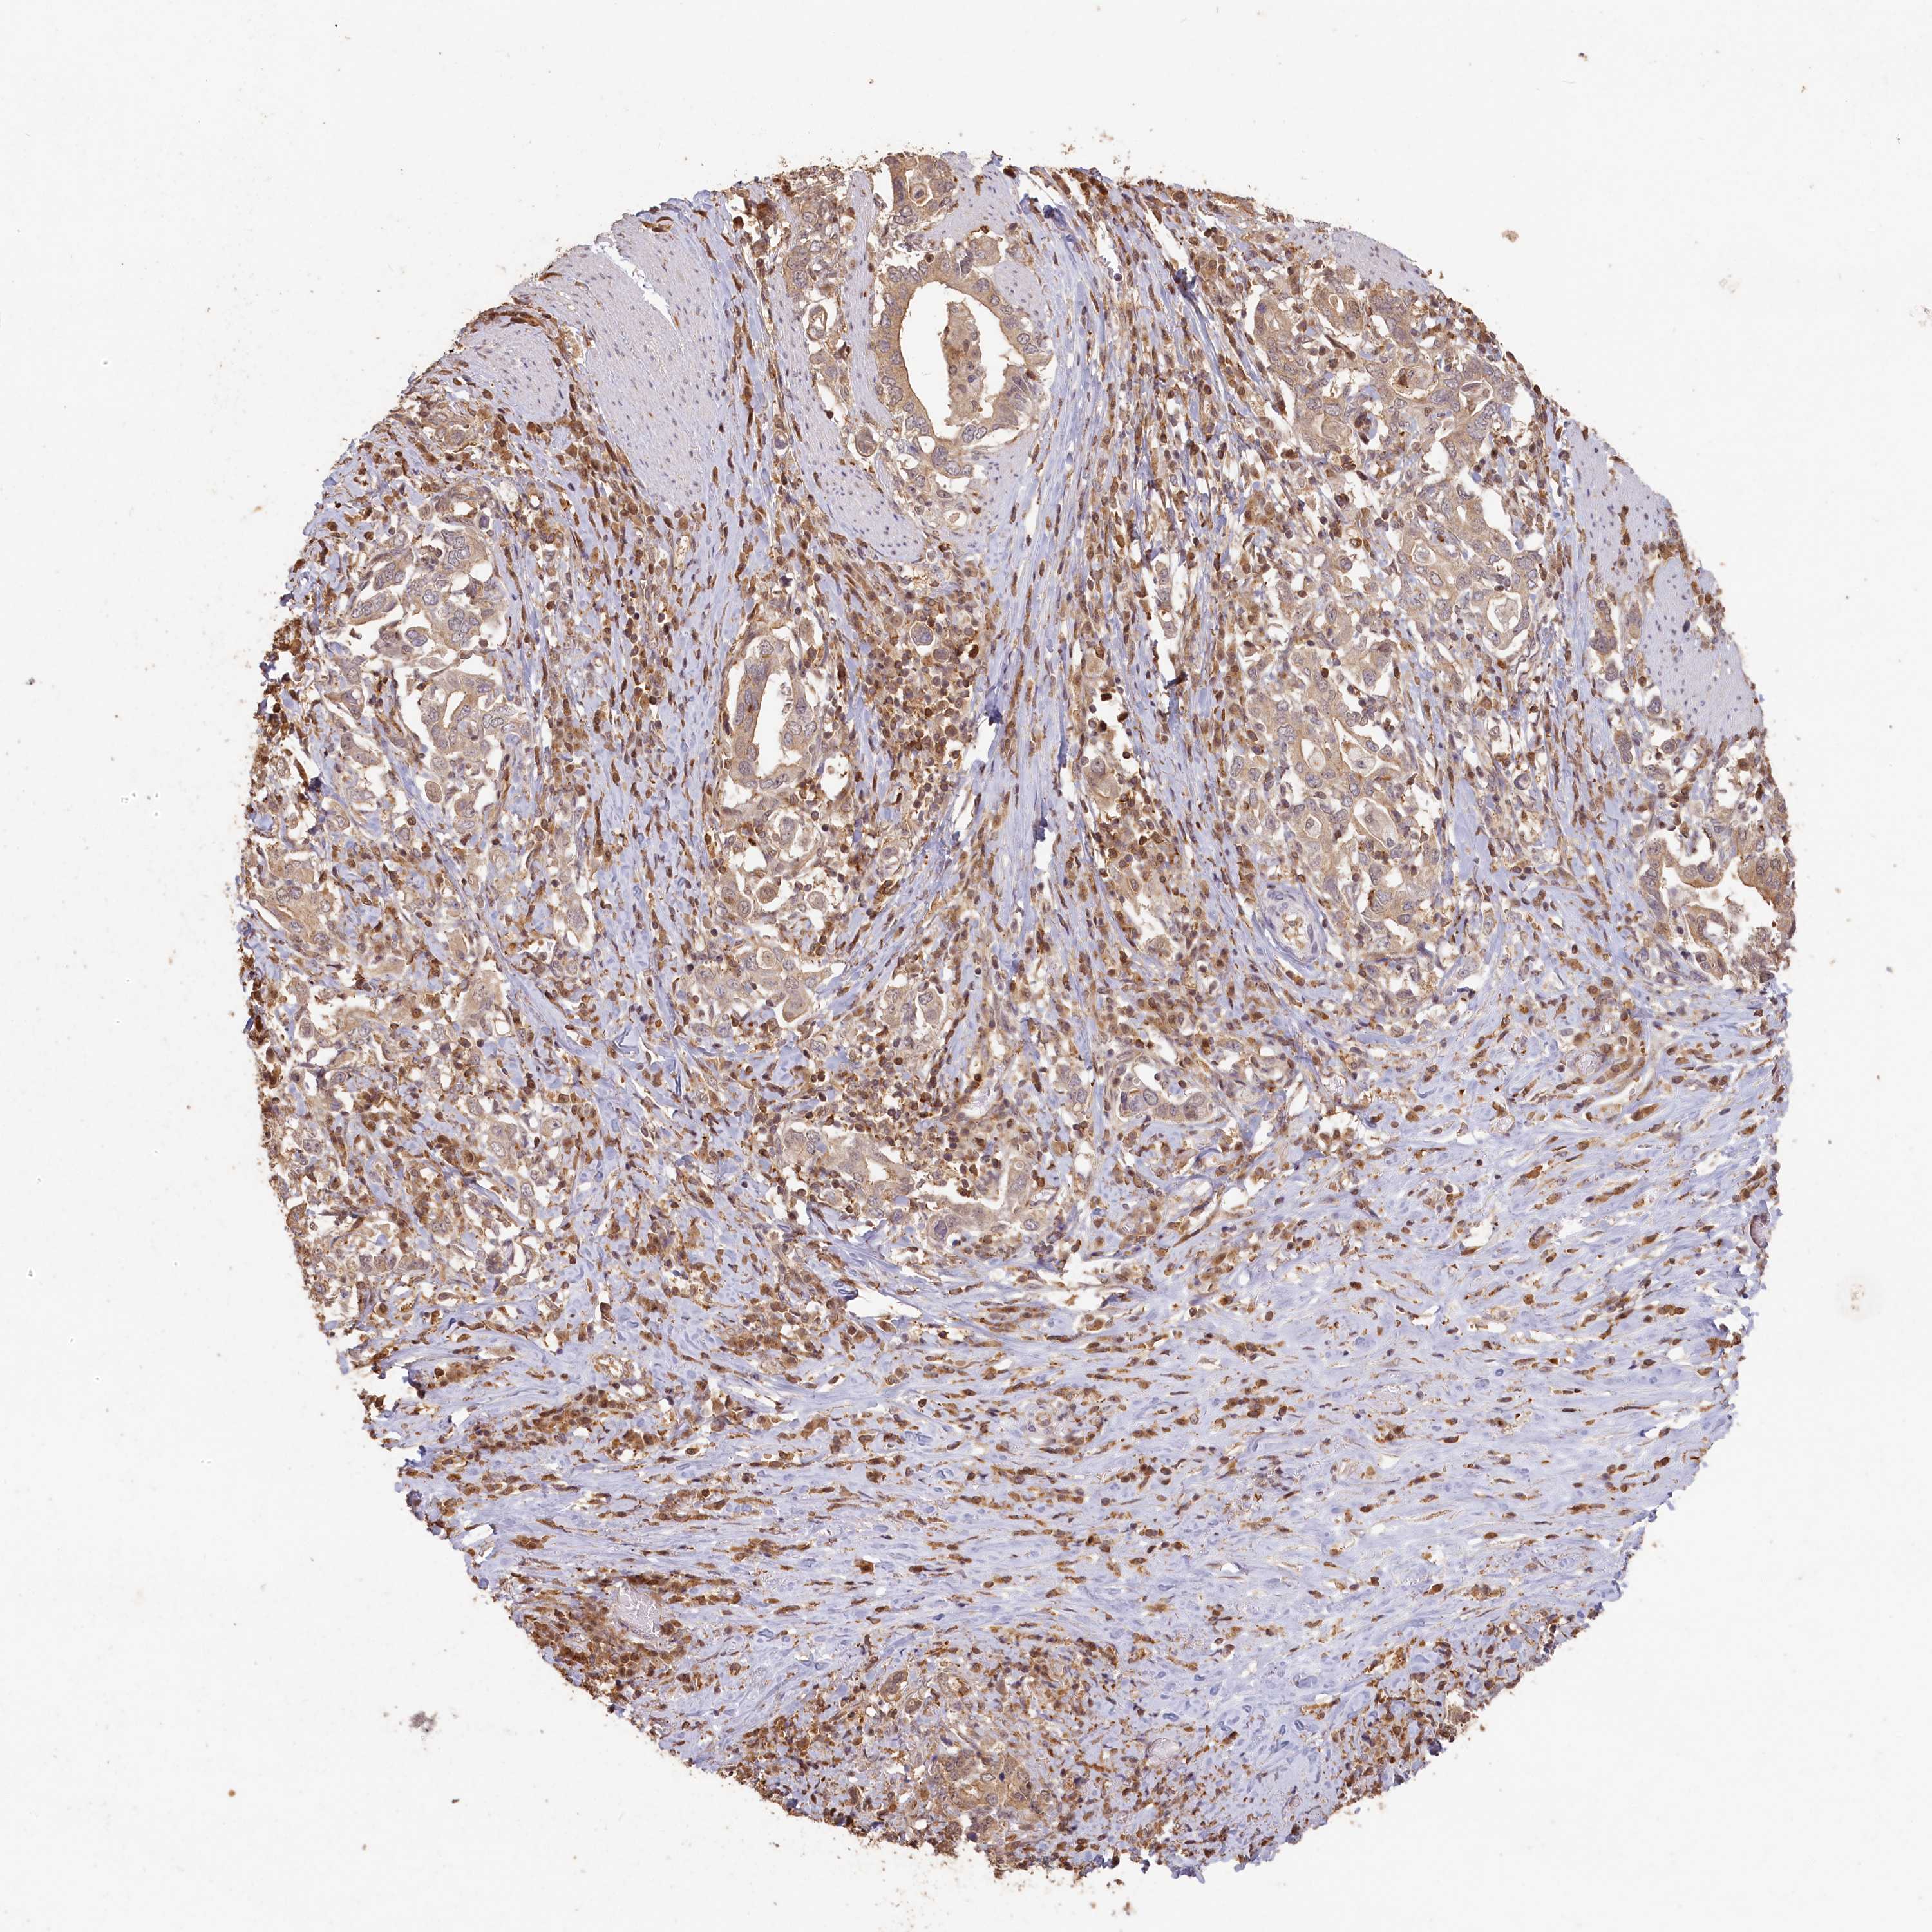

STOMACH CANCER - Protein expressioni

A mouse-over function shows sample information and annotation data. Click on an image to view it in a full screen mode. Samples can be filtered based on level of antibody staining by selecting one or several of the following categories: high, medium, low and not detected. The assay and annotation is described here.

Antibody stainingi

Antibody staining in the annotated cell types in the current human tissue is reported as not detected, low, medium, or high, based on conventional immunohistochemistry profiling in selected tissues. This score is based on the combination of the staining intensity and fraction of stained cells.

Each image is clickable and will lead to virtual microscopy that enables deeper exploration of all samples and also displays staining intensity scores, fraction scores and subcellular localization as well as patient and tissue information for each sample.

Antibody HPA038568

Staining

High

Medium

Low

Not detected

Intensity

Strong

Moderate

Weak

Negative

Quantity

>75%

75%-25%

<25%

None

Location

Nuclear

Cytoplasmic/membranous

Cytoplasmic/membranous,nuclear

Adenocarcinoma, NOS